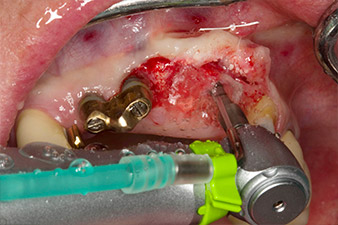

pilot drilling is performed with the new Implantmed and the WS-56 L contra-angle handpiece

Fig. 2: Two months later the pilot drilling is performed with the new Implantmed and the WS-56 L contra-angle handpiece (programme P1, ratio 1:1). The cooling is performed via the spray tube positioned on the left (for right-handed users).

Following primary healing, the soft tissues were shaped using the basally lined bridge. Two months later the site was exposed by a slightly palatal alveolar ridge incision (Fig 2). The dimensions of the alveolar bone proved to be sufficient at position 22. Figures 2 and 4 show the preparation of the implant bed, the tapping and the implantation using Implantmed.